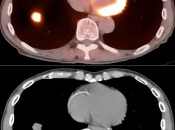

Potential Lesions in Solid Organs:

Assessment of a potential malignant lesion within most solid organs involves comparing the metabolic activity of the lesion to the background uptake within that organ (e.g. if a potential liver lesion’s metabolic activity is greater than the background activity of the liver, then the lesion is highly suspicious for malignancy).

There are a few exceptions to this rule, which are addressed in the The Cancers section. For example, many adrenal lesions are assessed by comparing their activity to the liver, not to the adrenal gland itself.